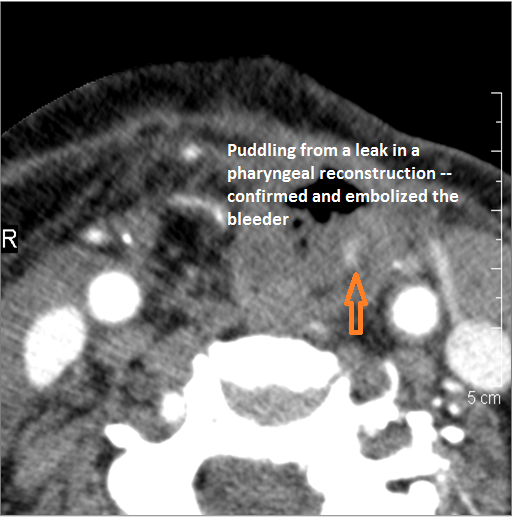

There is evidence of active extravasation from an arterial or venous source.